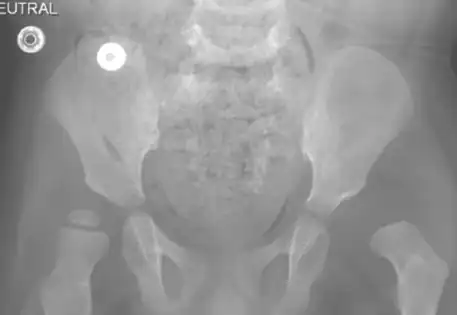

Hip dysplasia can manifest in various syndromes, including Prader-Willi syndrome, arthrogryposis, caudal regression syndrome, and Kabuki syndrome. Syndromic hip dysplasia cases in Dubai often involve more pronounced anatomical distortions, posing greater challenges in treatment and higher recurrence risks. Dr. Qureshi, a child orthopaedic doctor in Dubai, is experienced in addressing these complex cases, providing specialised care and management for each unique condition.

Dr. Qureshi has successfully managed numerous cases of syndromic hip dysplasia, employing investigations such as arthrography and CT imaging to assess reconstruction feasibility and plan surgical interventions. The treatment strategy is customarily crafted as a tailored combination of different techniques to address distinct components and contributory factors contributing to the dislocation.